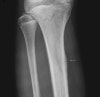

영상 검사

경골(Tibia)의 AP, lateral view 촬영을 합니다.

손상 후 3주는 지나야 X-ray에서 병변이 나타납니다.

통증이 심하지 않은 경우는 심한 일상생활활동을 제한시키면서 3~4주 후에 X-ray 검사를 다시 합니다.

X-ray : Tibial stress fracture

영상의학적 소견은 반드시 '통증과 압통이 있는 부위 검진'의 임상소견과 같이 고려해야 합니다.

다리에 반복적인 스트레스가 가해지는 신체활동을 하는 운동선수의 경우 종종 증상이 없는 부위에서도 음영증가 소견이 나올 수 있습니다.